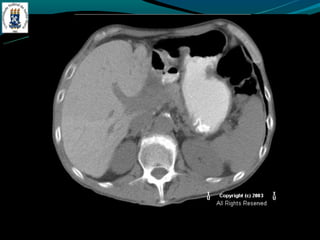

-   TC: densidade menor do que do baço

-   RM: identificar esteatose focal

-Esteatose focal

-   Distribuição segmentar, sub capsular, VB, lig falciforme

-   Margem nítida e em linha reta

-   Não desloca vasos

DOENÇA DO FÍGADOGORDUROSO -E uma resposta uma lesão e a toxina -Acúmulo de colesterol e triglicerídios -Alcoolismo, obesidade, desnutrição, hiperalimentação, costicóide, DM, pancreatite … -Exames de imagem é o melhor método -Avaliação: - TC: densidade menor do que do baço - RM: identificar esteatose focal -Esteatose focal - Distribuição segmentar, sub capsular, VB, lig falciforme - Margem nítida e em linha reta - Não desloca vasos